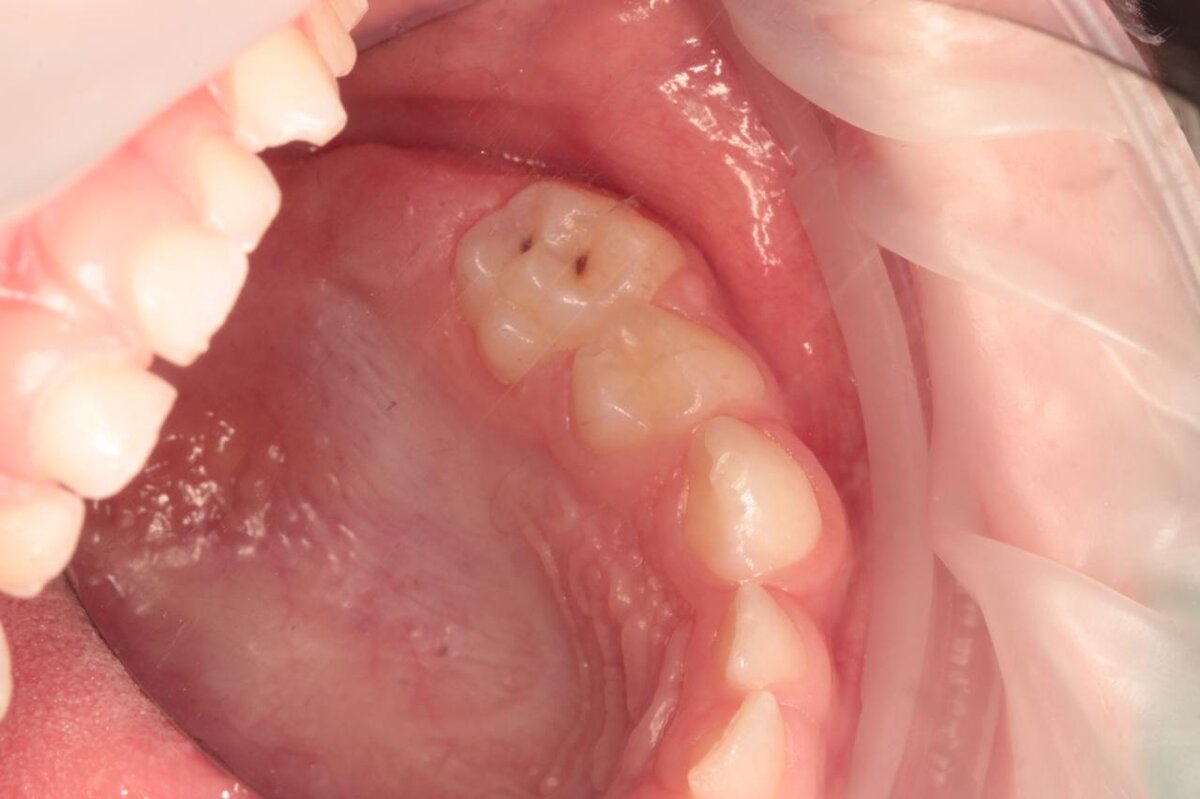

Молочные зубы также важны, как и постоянные. Прежде всего, молочные зубы имеют более тонкую эмаль, поэтому они очень уязвимы к кариесу и другим воздействиям. #Кариес на молочных зубах может осложняться пульпитом и периодонтитом, из-за которых могут появляться кисты в прикорневой зоне, а также поражаться зачаток постоянного зуба.

На начальных стадиях кариес лечится без препарирования тканей – реминерализация эмали, а также современная технология, позволяющая проводить пломбирование без сверления, легко справляются с кариозными поражениями эмалевого слоя. На более поздних стадиях, а также в случае пульпитов и периодонтитов, потребуется лечение молочных зубов с препарированием тканей. Бояться не стоит – современные методы анестезии позволяют провести их полностью безболезненно и комфортно для маленького пациента.